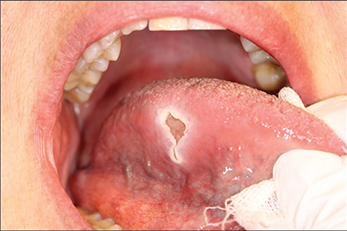

In June 2015, the patient reported increased pain from the enlarged ulcer without improvement of symptoms. A new excision was performed (Figure 2a), where HPE did not show any signs of dysplasia, but revealed an ulceration with fibrinous crusta, inflammation, and extensive infiltrates of neutrophil granulocytes (Figure 2b and c). At a revisit in September 2015, there was an ulcer with fungal infection. Fluconazole was administered, and the patient was called in for re-examination in December 2015. At that point, the lesion had developed an exophytic appearance on the lateral side of the tongue (Figure 3). In February 2016, treatment with radiofrequency ablation of the tongue was carried out (Figure 4). HPE displayed moderately to severely inflamed mucosa, with fibrosis and an ulcer consisting of eosinophil-rich infiltrates with candida infection. There were still no signs of malignancy or dysplasia. Antimycotics were administered.

Fig 2

Figure 2. (a) In June 2015 an increase in size of the ulcer was seen and an excision was performed. (b) & (c) Micrographs showing ulceration with fibrinous crusta and infiltrate of neutrophil granulocytes. Hematoxyline and eosin staining at × 40 (2b) and × 400 (2c).

Furthermore, in February 2018, another excision biopsy was retrieved from the lesion on the tongue, with an inquiry regarding IgG4-positive plasma cell levels. Histopathological analysis revealed that the tumor-like lesion on the tongue was caused by a candidiasis-associated ulceration. The ulceration formed an extruding polyploid lesion with granulation tissue rich in neutrophil granulocytes and lymphoplasmacytic cells (Figure 8a and b). The presence of plasma cells was demonstrated by CD138 and CD38 immunostainings. Eosinophils could be seen; however, there were no signs of granuloma or vasculitis. IgG-positive plasma cells were observed a few millimeters from the ulceration, further strengthening the suspicion of IgG4-RD (28, 29).

Fig 7

Figure 8. (a) & (b) Micrographs showing ulceration with extruding granulation tissue on the left, and normal epithelial surface with slight lymphoplasmacytic infiltrate underneath on the right. Hematoxyline and Eosin staining at x 40 (8a) and x 400 (8b).